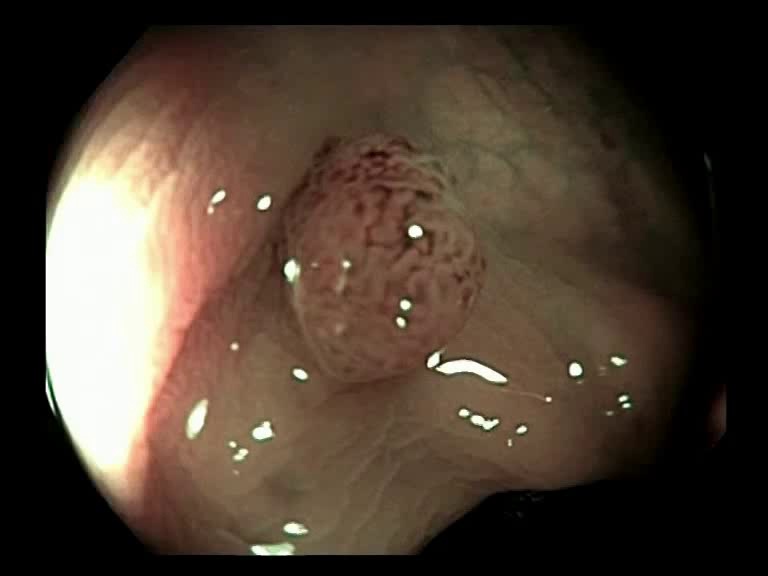

Figure 3: Key-frames obtained by our method and their corresponding depth maps. The polyp is visible from different viewing angles in these selected frames.

The selected key-frames are finally used to reconstruct the 3D surface of the polyp. We have used Facebook’s 3D image GUI to view the reconstructed polyp surface, the link to the video is shown here: https://youtu.be/PJKfk0Mqu2I\href https://youtu.be/PJKfk0Mqu2I. 3D visualization of a polyp helps in surgeries involving the removal of the polyp from its root. This gives better visualization of polyps for diagnosis. Fig. 3 shows some of the results of key-frame extraction and the corresponding depth maps. No publicly available datasets or methods using them that predict depth maps from endoscopic frames exist. Thus, a comparison between different methods for predicting depth from endoscopic images couldn’t be performed.